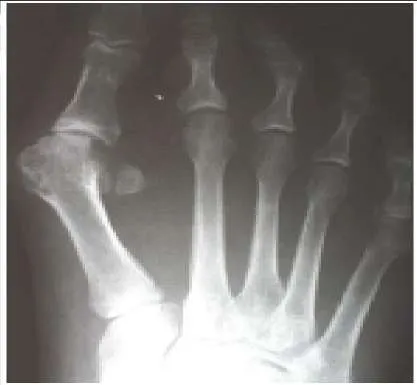

A 59-year-old woman presents for treatment of a painful hallux valgus deformity. She has a prominent bunion, normal motion of the hallux metatarsophalangeal (MP) joint, and painful callosity under the second MP joint. Radiographs of the foot are presented. The recommended treatment is:

This patient has probable instability of the metatarsocuneiform joint manifested by the overload phenomenon of the second metatarsal. Although this is not a sufficient indication for performing an arthrodesis of the metatarsocuneiform joint (modified Lapidus procedure), other findings of second metatarsal overload, including thickening of the cortex of the second metatarsal and instability of the first metatatarsocuneiform joint, should be looked for in addition to hypermobility of the first ray.